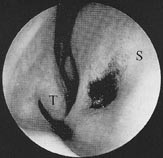

Det vomeronasale organ er imidlertid en dårlig definert struktur hos mennesket. Avhengig av undersøkelsesmetode er organet funnet hos 6 – 100 % av forsøkspersonene (32 – 35). Organet kan sees ved fremre rhinoskopi, men er betydelig lettere å identifisere med endoskopisk teknikk (fig 7) (34). Åpningen til det vomeronasale organ sitter på fremre tredel av neseskilleveggen 1 – 2 cm bak neseåpningen og 0,5 – 1,0 cm over gulvet i nesehulen. Fra denne åpningen går det en kanal som strekker seg ca. 5 mm bakover og ender blindt (34). Organet er ikke omsluttet av en beinet eller brusket kapsel i vår art (31). Mikroskopisk undersøkelse av det humane vomeronasale organ viser et pseudolagdelt epitel med mikrovilli (lukteepitelet har cilier). Epitelet består av tre celletyper: lyse celler, mørke celler og basalceller (34). Det spekuleres på om de lyse cellene er reseptorceller, men hos mennesket mangler det bevis på dette (34, 35). Det mangler også anatomiske studier som gir sikre holdepunkter for en nervøs forbindelse fra det vomeronasale organ til hjernen. Det er heller ikke påvist noen aksessorisk luktelapp hos mennesket. Man har antatt at den aksessoriske luktelapp er tilbakedannet, men i senere år har det vært spekulert på om strukturen hos mennesket har en litt annen lokalisasjon enn hos andre arter (31).